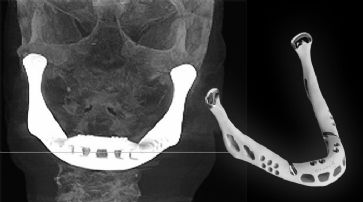

Erstes Kiefertransplantat mit 3D-Drucker hergestellt

Erstmals Operation bei 83 Jahre alter Patientin erfolgreich durchgeführt.

Ein 3D-Drucker hat ermöglicht, dass erstmals einem Menschen ein Unterkiefer transplantiert werden konnte. Der Eingriff wurde bereits im Juni an einer 83 Jahre alten Frau durchgeführt. Wissenschaftler der Universiteit Hasselt haben die OP jedoch erst jetzt öffentlich gemacht. Das Transplantat wurde von LayerWise aus Titanpuder hergestellt, erhitzt und mittels Laser Schicht für Schicht zusammengebaut.

Die Patientin litt an einer chronischen Knocheninfektion. Ihre Ärzte gingen davon aus, dass ein Eingriff mittels wiederherstellender Chirurgie aufgrund ihres Alters zu riskant sein würde und entschieden sich daher für das neue Verfahren. Das komplexe Implantat besteht aus Gelenken, Aussparungen, die das Muskelwachstum fördern sollen und Rillen, die das erneute Wachstum von Nerven und Venen steuern. Nach der Erstellung des Entwurfes dauerte der Ausdruck nur mehr wenige Stunden. «Nachdem wir das digitale 3D-Design erhalten hatten, wurde der Kiefer automatisch in 2D-Schichten aufgeteilt, die wir dann durch den Drucker geschickt haben», lässt sich Ruben Wauthle von LayerWise in einem BBC-Bericht zitieren. Für einen Millimeter an Höhe waren 33 Schichten erforderlich. Nach der Fertigstellung erhielt das Transplantat eine Biokeramikbeschichtung. Die Operation selbst dauerte vier Stunden und damit nur ein Viertel der Zeit, die sonst benötigt worden wäre. Der leitende Operateur, Jules Poukens, berichtet, dass die Frau bereits kurz nach der Operation einige Worte gesprochen hat und bereits einen Tag später wieder schlucken konnte.

Erste Operation mit künstlichem Kiefer. /

Nach vier Tagen wurde die Frau entlassen.

Organ-Druck als Ziel